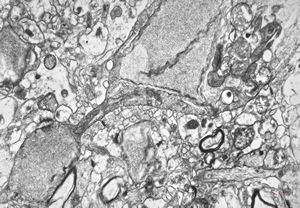

F,49y. | purulent meningitis- meningococcal v.s.

F,49y. | purulent meningitis- meningococcal v.s.

F,49y. | purulent meningitis- meningococcal v.s.